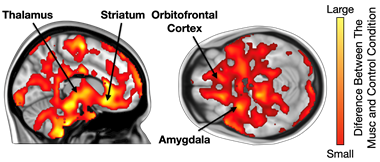

The study measured the release of opioids in the brain using positron emission tomography (PET) while participants listened to their favourite music. Additionally, functional magnetic resonance imaging (fMRI) was used to examine how the density of opioid receptors affects brain activation when listening to music.

The results show that favourite music influenced opioid release in several brain areas associated with the experience of pleasure. The release of opioids was also linked to how often participants reported experiencing pleasurable chills while listening to music. Furthermore, individual differences in the number of opioid receptors correlated with brain activation during music listening: the more opioid receptors participants had, the more strongly their brains reacted in MRI scans.